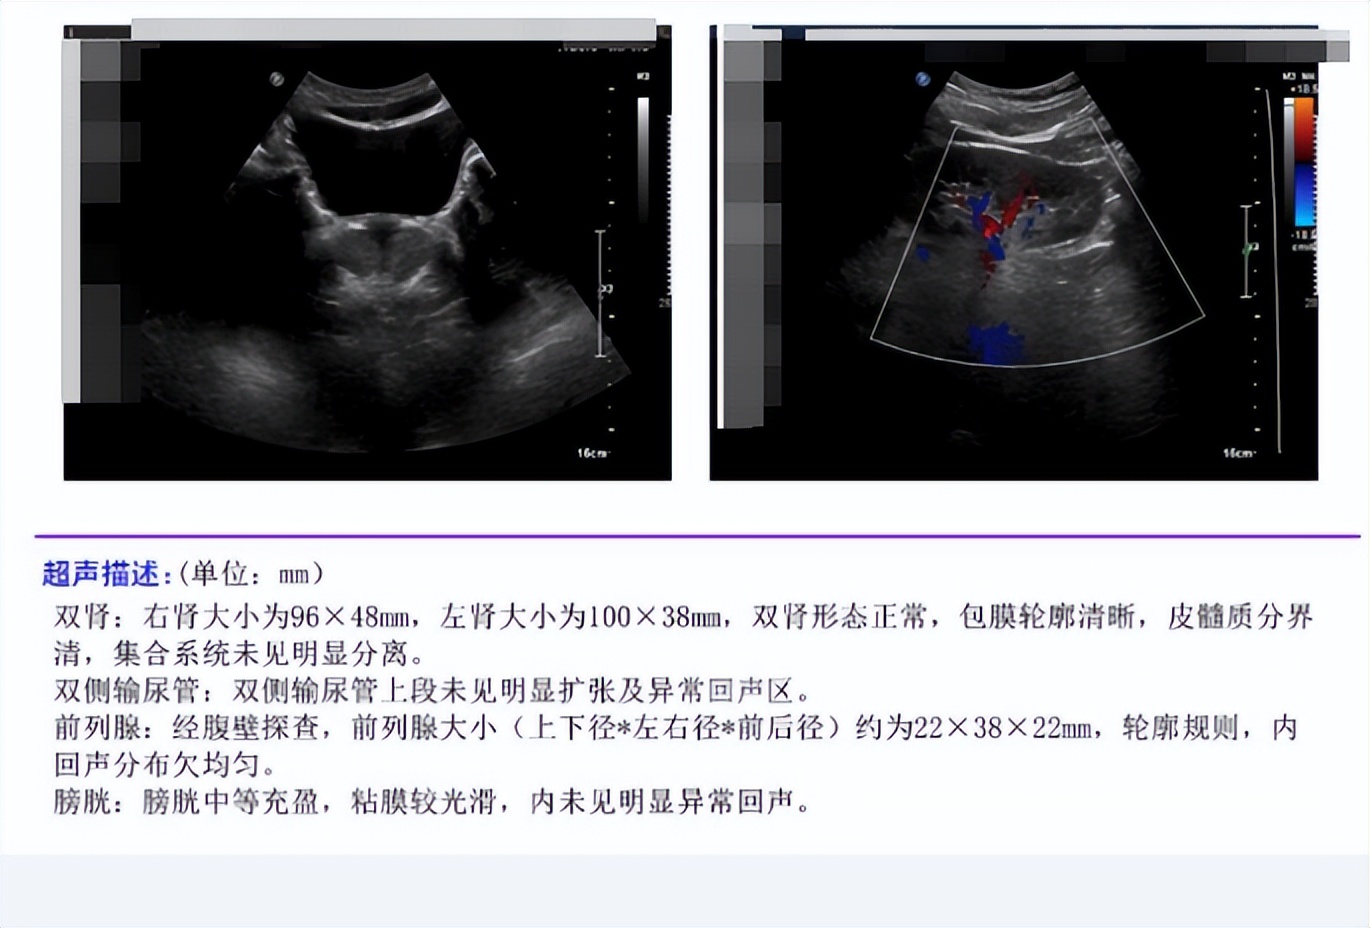

小陈在外院进行过前列腺液培养并没有发现细菌生长,属于非细菌性前列腺炎。我们进一步完善了尿常规、泌尿系彩超和前列腺肿瘤标记物(PSA),也没有发现异常。因此针对其较为明显的尿频和阳痿症状,我们为其开具了α受体阻滞剂和他达拉非等药物改善症状。